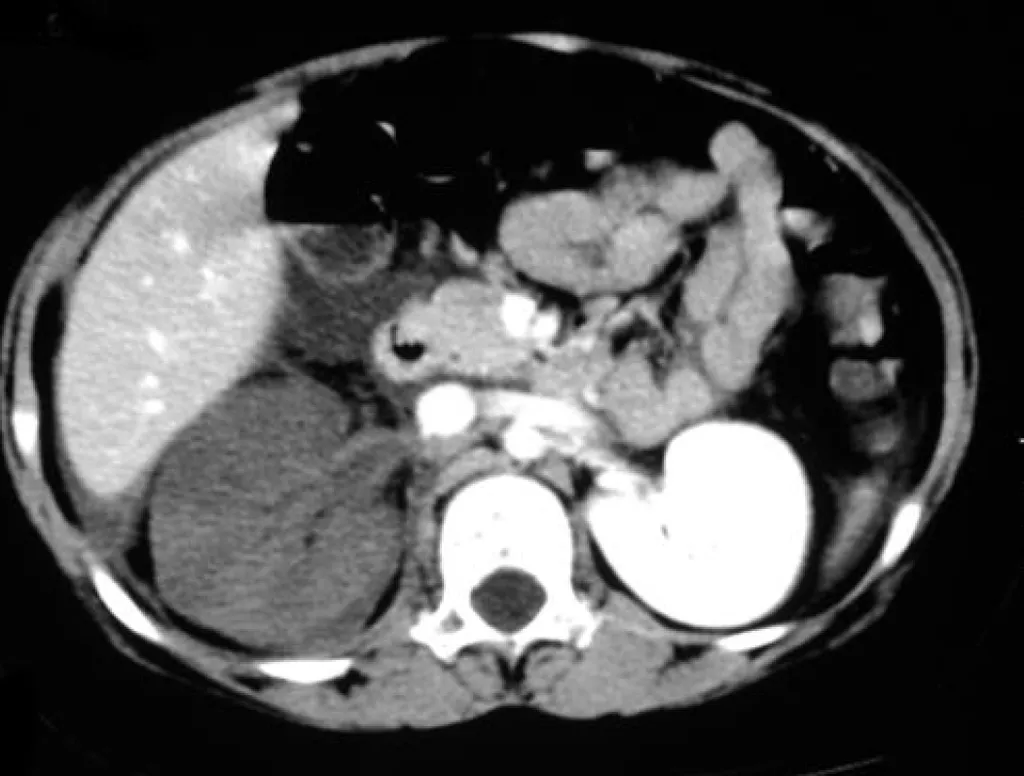

破題關鍵

這題的解題核心在於辨識電腦斷層掃描影像中,左右兩側腎臟對比劑灌注的差異。圖片顯示右腎幾乎沒有對比劑強化,而左腎則正常強化,這強烈暗示右腎的血流供應出了問題。

選項拆解